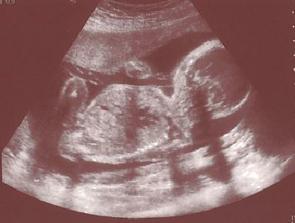

25.7. Velký ultrazvuk - mám všechno - játra, ledviny, močovej měchýř a pindíka 😉 ...

Pan dochtor mě zase pobavil - změřil mi hlavu, změřil mi nožičku a řek že tím pádem vážím 1610 g 😀 😀 (tři listy a dva stonky - to máme pět dní domácího vězení, uííí ťap ťap, "achoooj" řekla Žlababa )